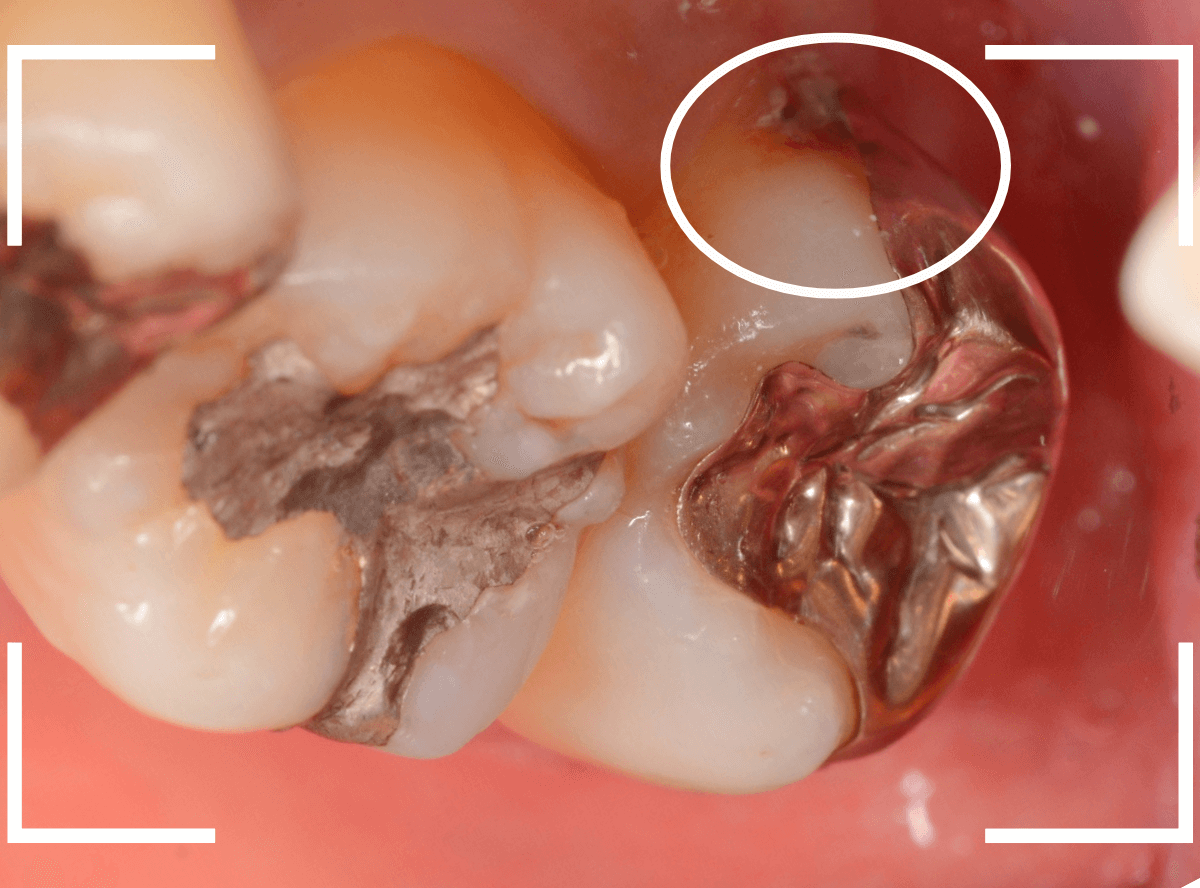

Case.14 インレーの下の歯肉まで広がった虫歯

「下の奥歯が噛むと痛む」という症状で来院された患者さんのケースです。

お口の中の状態を確認すると、奥歯の端に穴が開いているのが見えます。

ここかな?

レントゲン写真で確認します。

やはり、奥歯の端が大きな虫歯になっています。

青いラインが歯の神経、赤いラインが虫歯です。

レントゲン写真上では虫歯が神経まで達しているように見えます。

これは、神経を取らないとダメかもしれません。